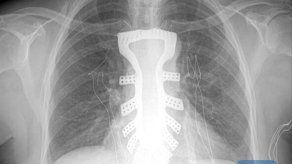

Médicos chinos implantan con éxito un esternón fabricado con impresora 3D